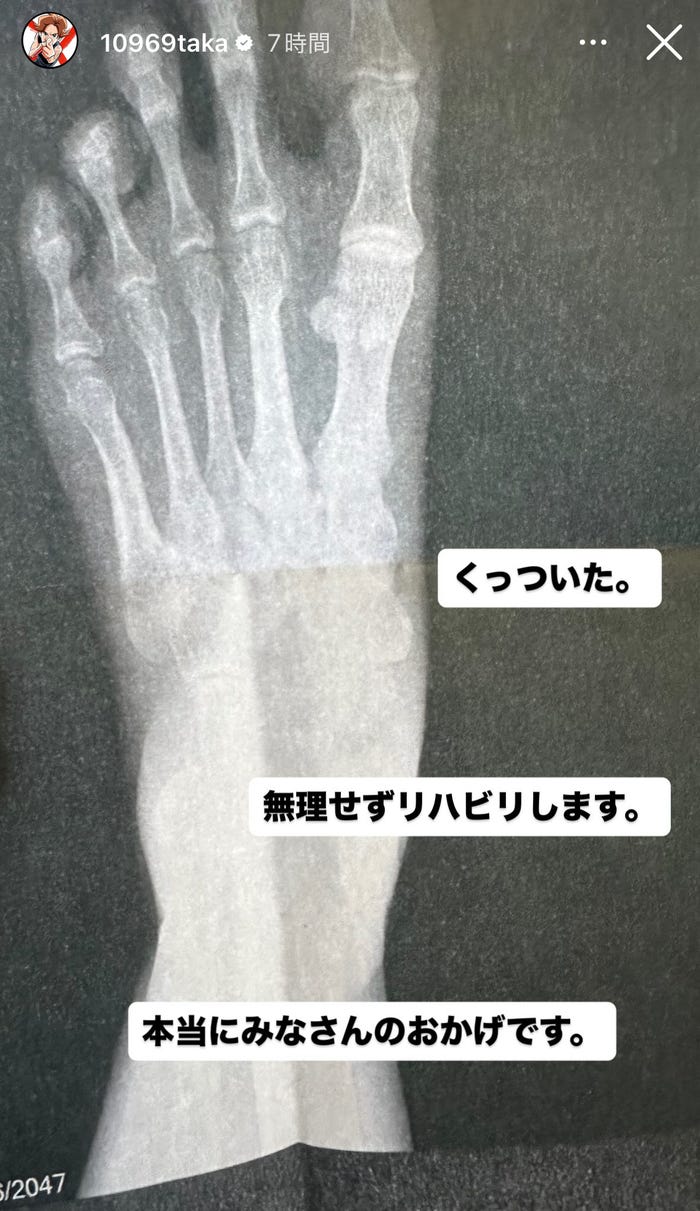

ONE OK ROCKのボーカル・Takaが10月2日、自身のInstagramストーリーズを更新。骨折の経過を報告した。

8月31日に開催された日本ツアー「ONE OK ROCK DETOX JAPAN TOUR 2025」の日産スタジアム公演にて左足の小指を骨折したことを自身のInstagramで報告していたTaka。骨折から約1ヶ月が経過しTakaは「くっついた。無理せずリハビリします。本当にみなさんのおかげです」と投稿。足のレントゲン写真も公開し現在の経過を伝えている。Taka、公演中に左足小指を骨折していた

8月31日に投稿した動画で「Delusion:All」の歌唱中に小指の付け根が折れてしまったことを明かし「歌ってるときに後ろに足ついたときにものすごい勢いでグチャッとなった。『あっ』となったんですけど…みなさんにはみっともない姿を見せてしまった」と当時の状況を説明した。(modelpress編集部)